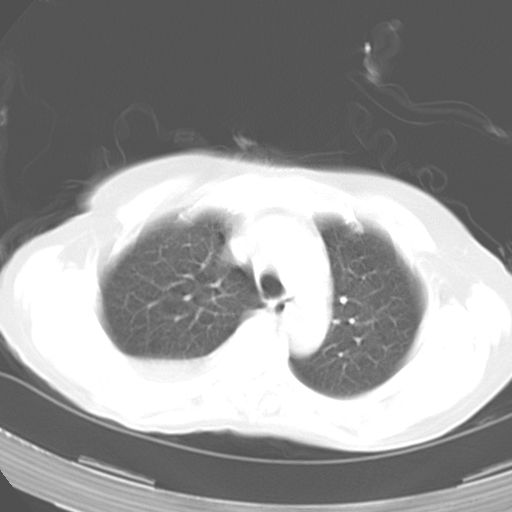

以下是引用dyqct在2006-12-7 21:08:00的发言:[br]考虑:1、肝内外胆管多发性结石伴肝左叶外侧段肝萎缩;[br] 2、右膈下多发脓肿;[br] 3、右侧少量胸腔积液、斜裂积液;[br] 4、左肾囊肿。

以下是引用jiazh在2006-12-7 20:37:00的发言:[br]肝脏周围半狐形低密度影,肝脏表面受压推移,考虑膈下脓肿可能性大;2、右侧胸腔积液

以下是引用拾荒者在2006-12-7 21:44:00的发言:[br]肝内外胆管多发结石,右膈下多发脓肿,右胸膜腔及叶间裂积液,左肾囊肿。[br] [br]